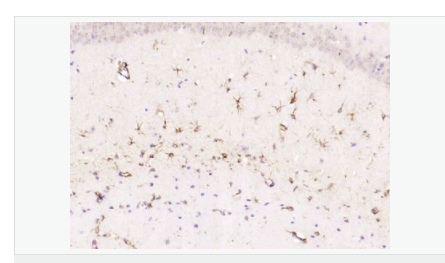

| 產(chǎn)品應用 | WB=1:500-2000 ELISA=1:5000-10000 IHC-P=1:200-1000 IHC-F=1:200-1000 Flow-Cyt=1μg/Test ICC=1:100 IF=1:200-800 (石蠟切片需做抗原修復) not yet tested in other applications. optimal dilutions/concentrations should be determined by the end user. |

| 產(chǎn)品介紹 | This gene encodes one of the major intermediate filament proteins of mature astrocytes. It is used as a marker to distinguish astrocytes from other glial cells during development. Mutations in this gene cause Alexander disease, a rare disorder of astrocytes in the central nervous system. Alternative splicing results in multiple transcript variants encoding distinct isoforms. [provided by RefSeq, Oct 2008] Function: GFAP, a class-III intermediate filament, is a cell-specific marker that, during the development of the central nervous system, distinguishes astrocytes from other glial cells. Subunit: Interacts with SYNM. Isoform 3 interacts with PSEN1 (via N-terminus). Subcellular Location: Cytoplasm. Note=Associated with intermediate filaments. Tissue Specificity: Expressed in cells lacking fibronectin. Post-translational modifications: Phosphorylated by PKN1. DISEASE: Defects in GFAP are a cause of Alexander disease (ALEXD) [MIM:203450]. Alexander disease is a rare disorder of the central nervous system. It is a progressive leukoencephalopathy whose hallmark is the widespread accumulation of Rosenthal fibers which are cytoplasmic inclusions in astrocytes. The most common form affects infants and young children, and is characterized by progressive failure of central myelination, usually leading to death usually within the first decade. Infants with Alexander disease develop a leukoencephalopathy with macrocephaly, seizures, and psychomotor retardation. Patients with juvenile or adult forms typically experience ataxia, bulbar signs and spasticity, and a more slowly progressive course. Similarity: Belongs to the intermediate filament family. SWISS: P14136 Gene ID: 2670 Database links: Entrez Gene: 2670 Human Entrez Gene: 14580 Mouse Omim: 137780 Human SwissProt: P14136 Human SwissProt: P03995 Mouse Important Note: This product as supplied is intended for research use only, not for use in human, therapeutic or diagnostic applications. 星形膠質細胞標志物 (Astrocyte Marker) GFAP是一個56kDa的中間絲蛋白(intermediate filament,IF),在中樞神經(jīng)系統(tǒng)發(fā)育期是一個特異性的標志物,以區(qū)別星形細胞和其它膠質細胞。GFAP表達在皮層和海馬,急、慢性皮質酮治療時表達減少。 GFAP可以和人、大鼠、小鼠的GFAP反應,在正常和腫瘤性的星形膠質細胞陽性表達,而神經(jīng)節(jié)細胞、神經(jīng)元、成纖維細胞、少突膠質細胞和這些細胞來源的腫瘤細胞陰性表達,主要用于星形膠質瘤等中樞神經(jīng)系統(tǒng)腫瘤的診斷和鑒別診斷,GFAP的缺乏可導致AD病。 |